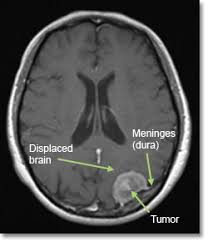

Increasing Incidence Of Aggressive Brain Tumour Glioblastoma Multiforme In England During 1995 2015 Lennart Hardell S Blog from lennarthardellenglish.files.wordpress.com What can i do to reduce my chances of getting brain cancer? In general, men are more likely than women to develop a brain tumor. Increased intracranial pressure (icp) vomiting (usually occurs in the morning without nausea) headache. A brain tumor, known as an intracranial tumor, is an abnormal mass of tissue in which cells grow and multiply uncontrollably, seemingly unchecked by the mechanisms that control normal cells. Normally, this gene prevents cells with damaged dna from growing. During this time, brain tumor data have been gathered by the national cancer institute from catchment areas representing 10% of the united states population. Recently, an increasing incidence of brain tumors has been reported from multiple studies. The death rate was 4.4 per 100,000 men and women per year.

Be aware of your risk. A brain tumor can form in the brain cells (as shown), or it can begin elsewhere and spread to the brain. This is the percentage of people. Brain cancer is an overgrowth of cells in your brain that forms masses called tumors. The rate of new cases of brain and other nervous system cancer was 6.4 per 100,000 men and women per year. These brain tumors are usually benign. Increased intracranial pressure (icp) vomiting (usually occurs in the morning without nausea) headache. A new study reports bigger brain size could mean an increased risk of developing brain cancer. Some of the common pediatric brain tumors include ependymoma, astrocytoma, medulloblastoma and brain cell glioma. Bigger brains have more brain cells, and thus a greater potential for cell mutations that lead to cancer. Brain cancer risk may increase for those exposed to solvents, pesticides, oil products, rubber, or vinyl chloride. Recently, an increasing incidence of brain tumors has been reported from multiple studies. A brain tumor, known as an intracranial tumor, is an abnormal mass of tissue in which cells grow and multiply uncontrollably, seemingly unchecked by the mechanisms that control normal cells.